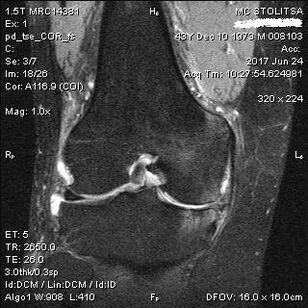

يتم تشخيص التهاب المفاصل في مفصل الركبة في مكتب طبيب الروماتيزم أو جراح العظام. يقوم الطبيب بفحص المفصل المصاب، وجسه، والاستماع إلى الشكاوى، وطرح أسئلة إضافية. يقوم بإجراء عدة اختبارات - على سبيل المثال، يطلب من المريض ثني ساقه أو المشي بضع خطوات. ومن ثم، إذا كان من الضروري توضيح مرحلة المرض أو طبيعة التغيرات المرضية، فسوف يحولك لإجراء دراسات إضافية. على سبيل المثال، للتصوير المقطعي أو التصوير الشعاعي.